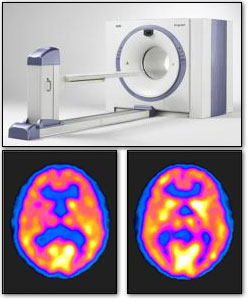

Pozitron Emissziós Tomográfia.

A képalkotó eljárások egyik típusa. A daganatos betegségek diagnózisának felállítására használják.

A beteg vénásan kis mennyiségű kontrasztanyagot - radioaktív glükózt (cukrot) kap, majd egy számítógéppel összekapcsolt pásztázóeszköz segítségével nagy részletességű képeket készítenek a test azon területeiről, amelyek felhasználják a cukrot. A rákos sejtek általában a normális sejteknél több glükózt igényelnek, így meghatározható a daganatos sejtek elhelyezkedése.